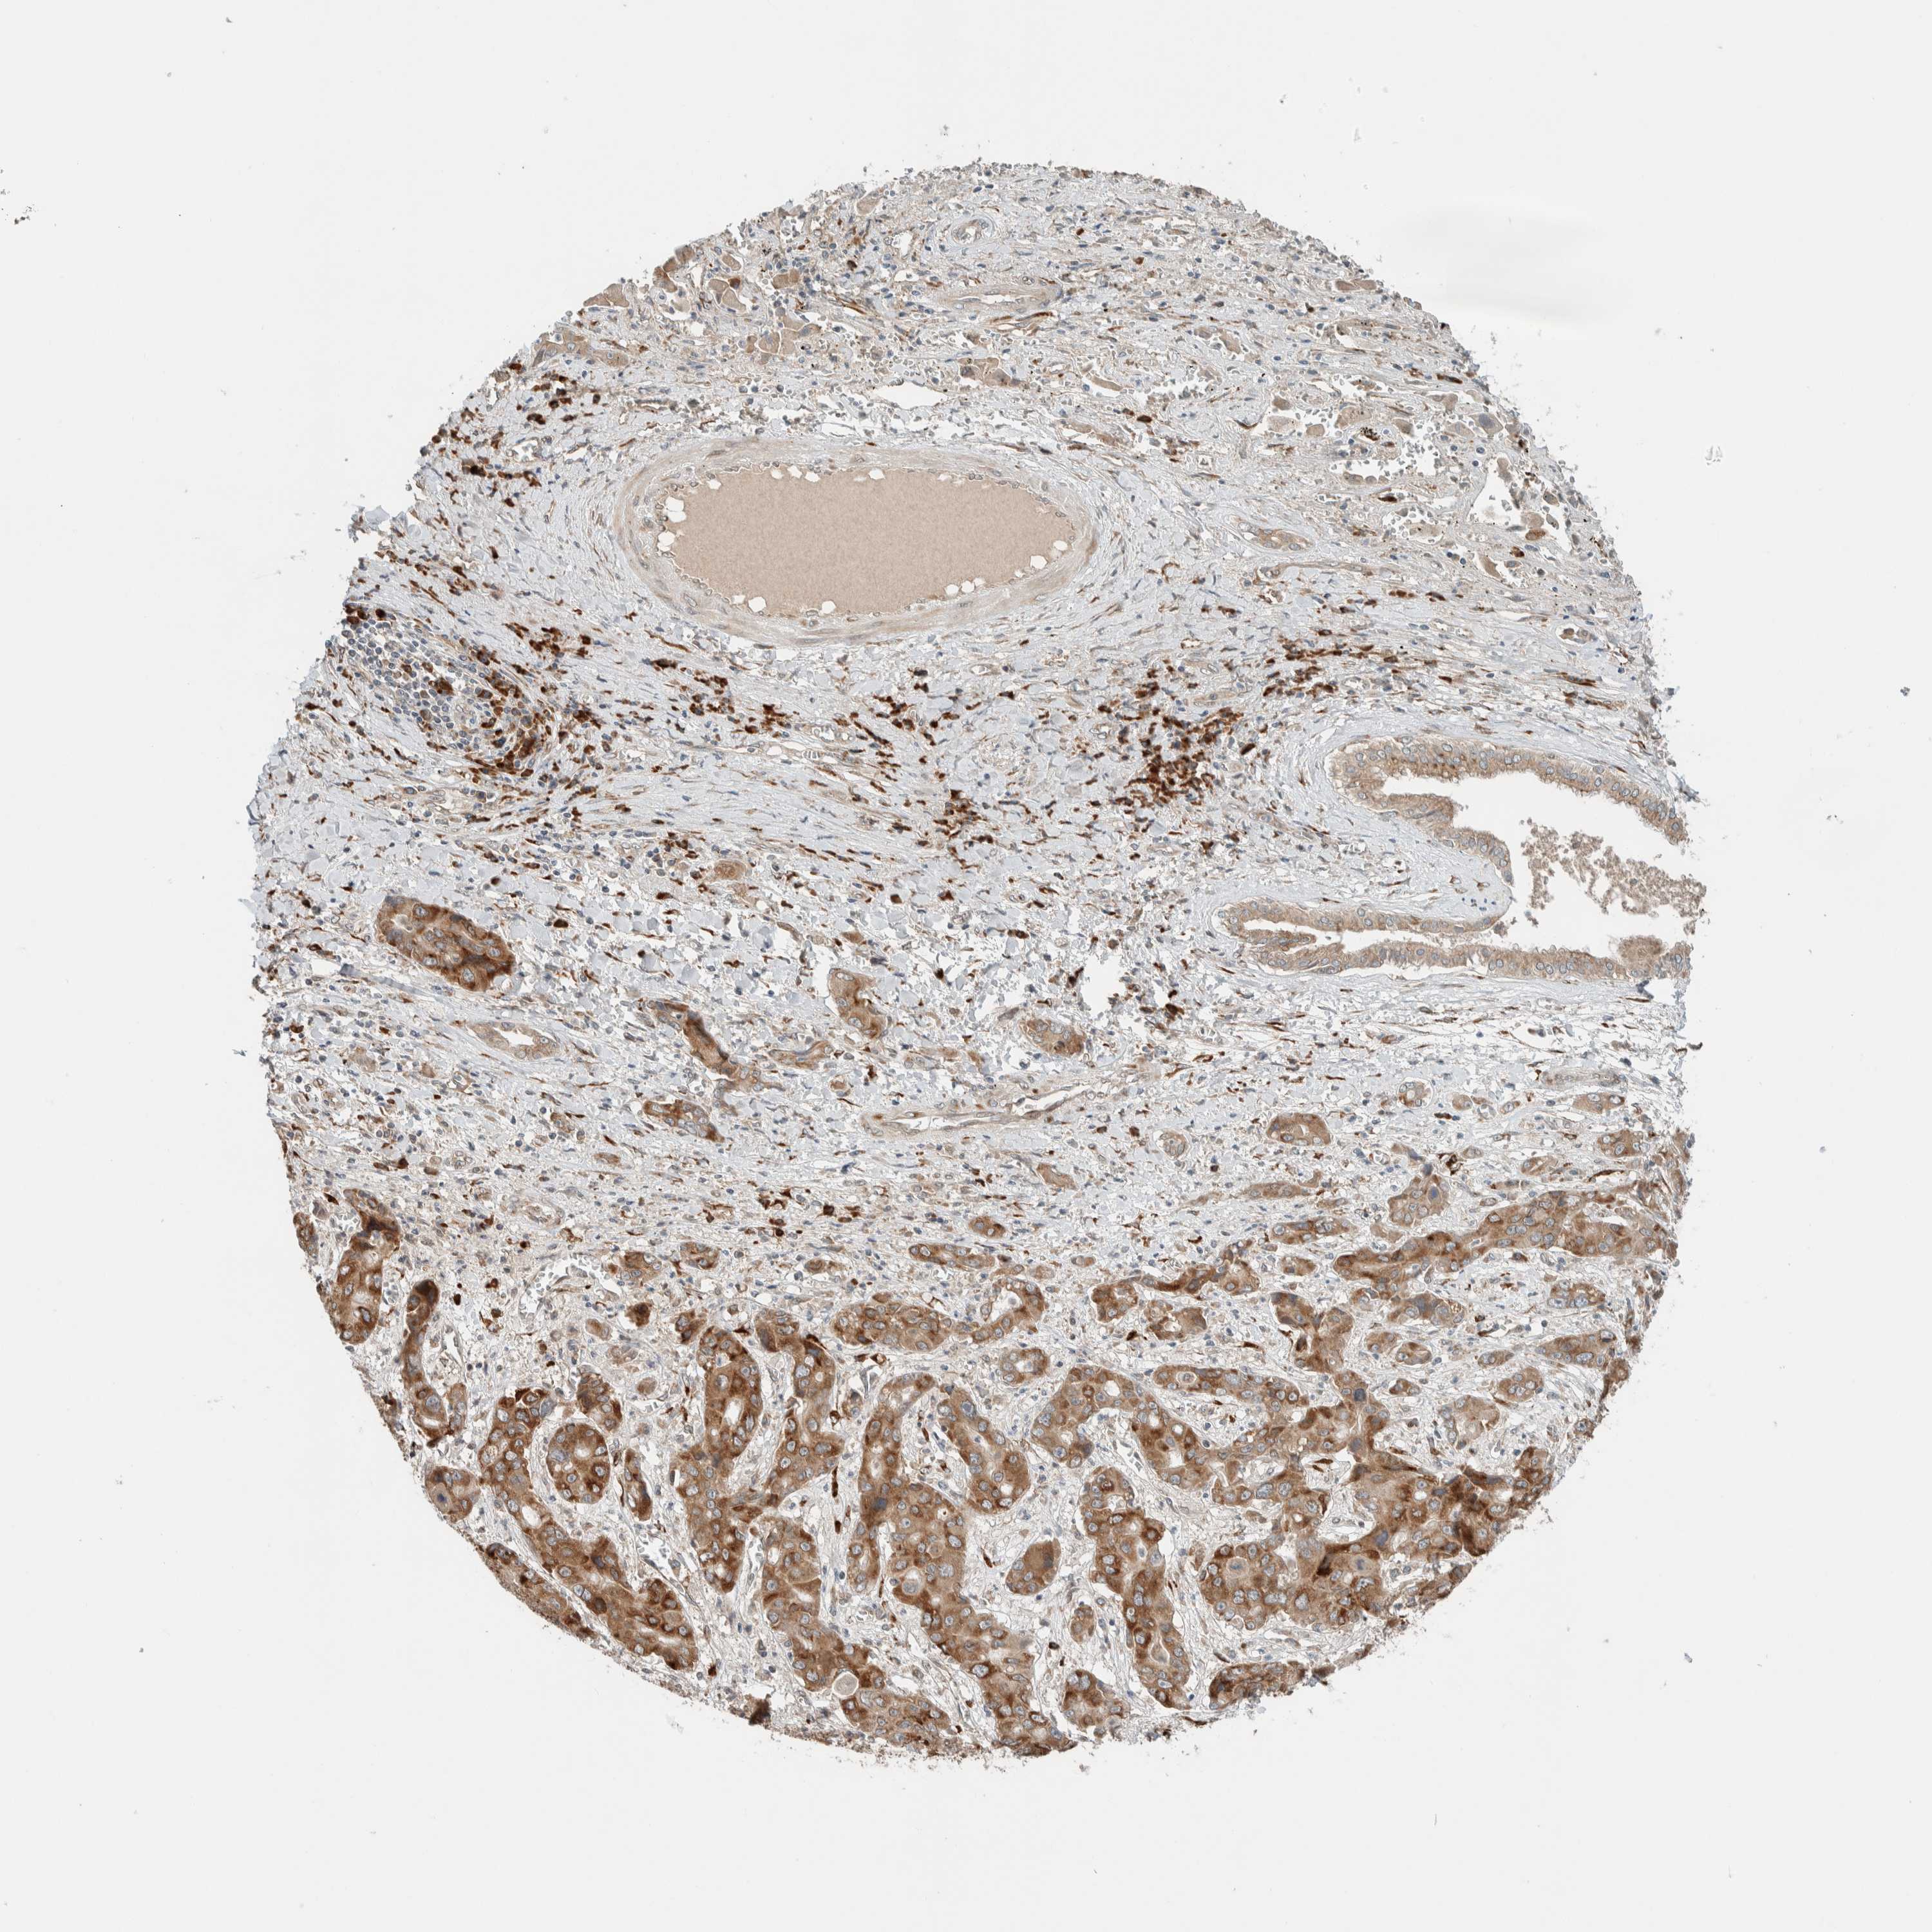

LIVER CANCER - Protein expressioni

A mouse-over function shows sample information and annotation data. Click on an image to view it in a full screen mode. Samples can be filtered based on level of antibody staining by selecting one or several of the following categories: high, medium, low and not detected. The assay and annotation is described here.

Note that samples used for immunohistochemistry by the Human Protein Atlas do not correspond to samples in the TCGA dataset.

Antibody stainingi

Antibody staining in the annotated cell types in the current human tissue is reported as not detected, low, medium, or high, based on conventional immunohistochemistry profiling in selected tissues. This score is based on the combination of the staining intensity and fraction of stained cells.

Each image is clickable and will lead to virtual microscopy that enables deeper exploration of all samples and also displays staining intensity scores, fraction scores and subcellular localization as well as patient and tissue information for each sample.

Antibody HPA023559

Antibody HPA023564

Antibody HPA044971

Antibody CAB031916

Cholangiocarcinoma

Carcinoma, Hepatocellular, NOS